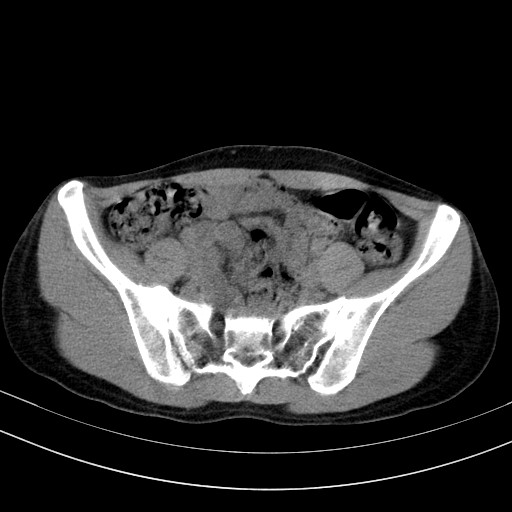

以下是引用卜一在2009-4-7 5:08:00的发言:[br]宫颈癌可能。支持!

以下是引用随光逐影在2009-4-7 8:17:00的发言:[br]考虑宫颈占位性病变(宫颈癌?);建议行进一步检查。

以下是引用jiangjing在2009-4-7 16:46:00的发言:[br]宫颈增大,结构不清,右侧附件区可疑囊样占位,建议增强及mri 检查